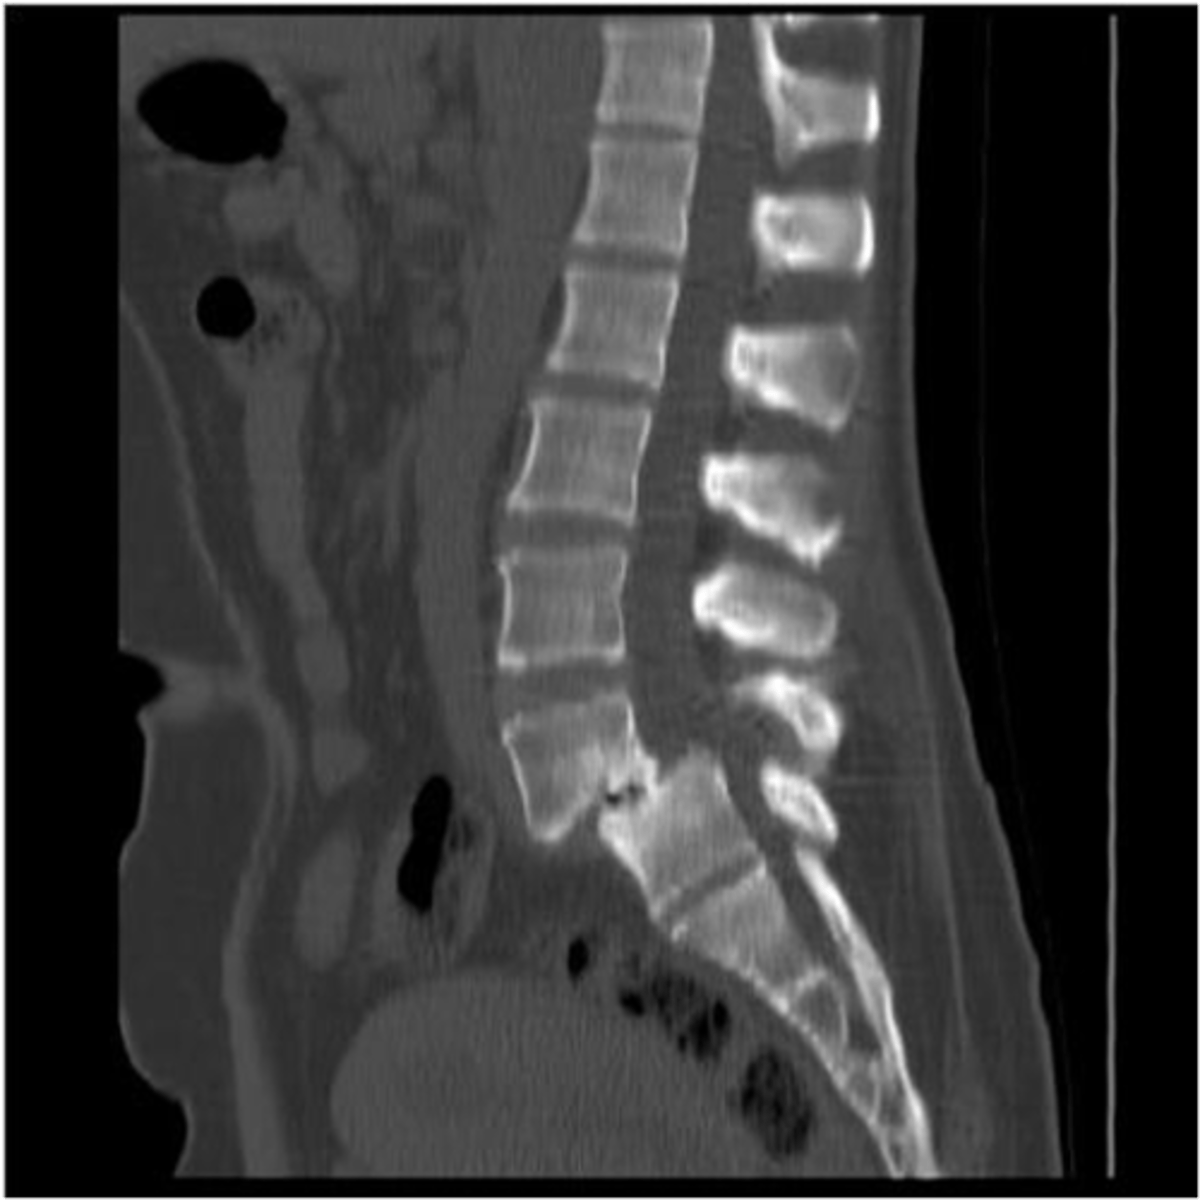

CT myelography can be used to evaluate the ____ and _____

spinal cord and canal

CT myelography is a good alternative to MRI to identify

spinal stenosis, disc herniation, spondylosis, arthritis

spinal stenosis

Narrowing of the spinal canal that causes pressure on the spinal cord (nerves)

spinal stenosis etiology

osteophytes, disc herniation, tumors, trauma